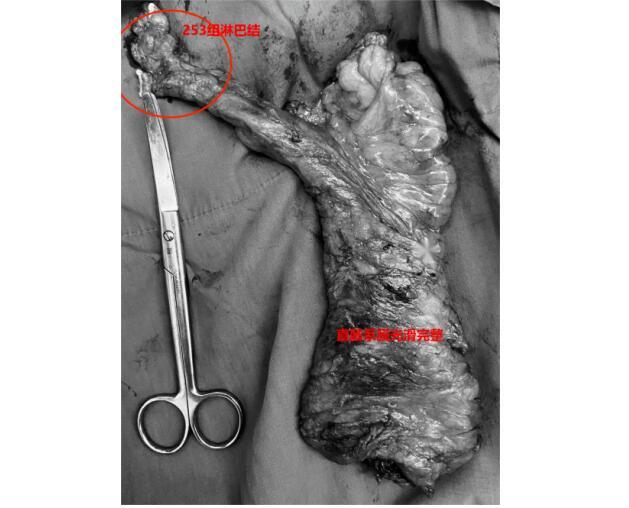

陈洪生教授凭借精湛的手术技巧和耐心细致的操作,在团队宝赛吉日呼主治医师、王中瑞住院医师的配合下,顺利通过腹腔镜完全经腹入路,自肠系膜下动脉左侧Toldt’s间隙-直肠后间隙-肛提肌上间隙,一直将直肠游离至直肠系膜终点,游离至肛提肌平面、括约肌间沟,将肿瘤提拉出肛提肌裂孔,从而获得了充足的下切缘,在保证肿瘤根治的基础上,顺利保住了肛门,同时保留了腹下神经和盆丛神经,最大程度保证术后肛门功能和排尿功能的恢复。手术层面十分清晰,观察肠管的血运良好,吻合确切。考虑到高龄患者日后再次进行手术和麻醉的风险,并没有进行保护性造口,而是留置了肛门减压管。在围手术期个体化、精细化管理下,术后第二日正常饮水,术后第五日开始进流食,在正常排便后逐步撤离了肛管和盆腔引流管,患者术后恢复良好,没有出现吻合口瘘,肛门的功能也保留完好。

81岁的周老(化名)因间断便血,肠镜检查发现直肠恶性肿瘤,肠镜及直肠核磁评估肿瘤距肛缘5cm,肿瘤的位置同样很低,患者及家属为求保肛手术治疗,慕名找到陈洪生教授。通过细致的术前评估和术前准备,在克服了男性骨盆狭窄等不利条件下,经过艰苦的努力,陈洪生教授团队再次成功实施了“腹腔镜完全经腹入路直肠括约肌间切除术(ISR)”,既切除了直肠的恶性肿瘤,又极限地保留了肛门和肛门的功能。